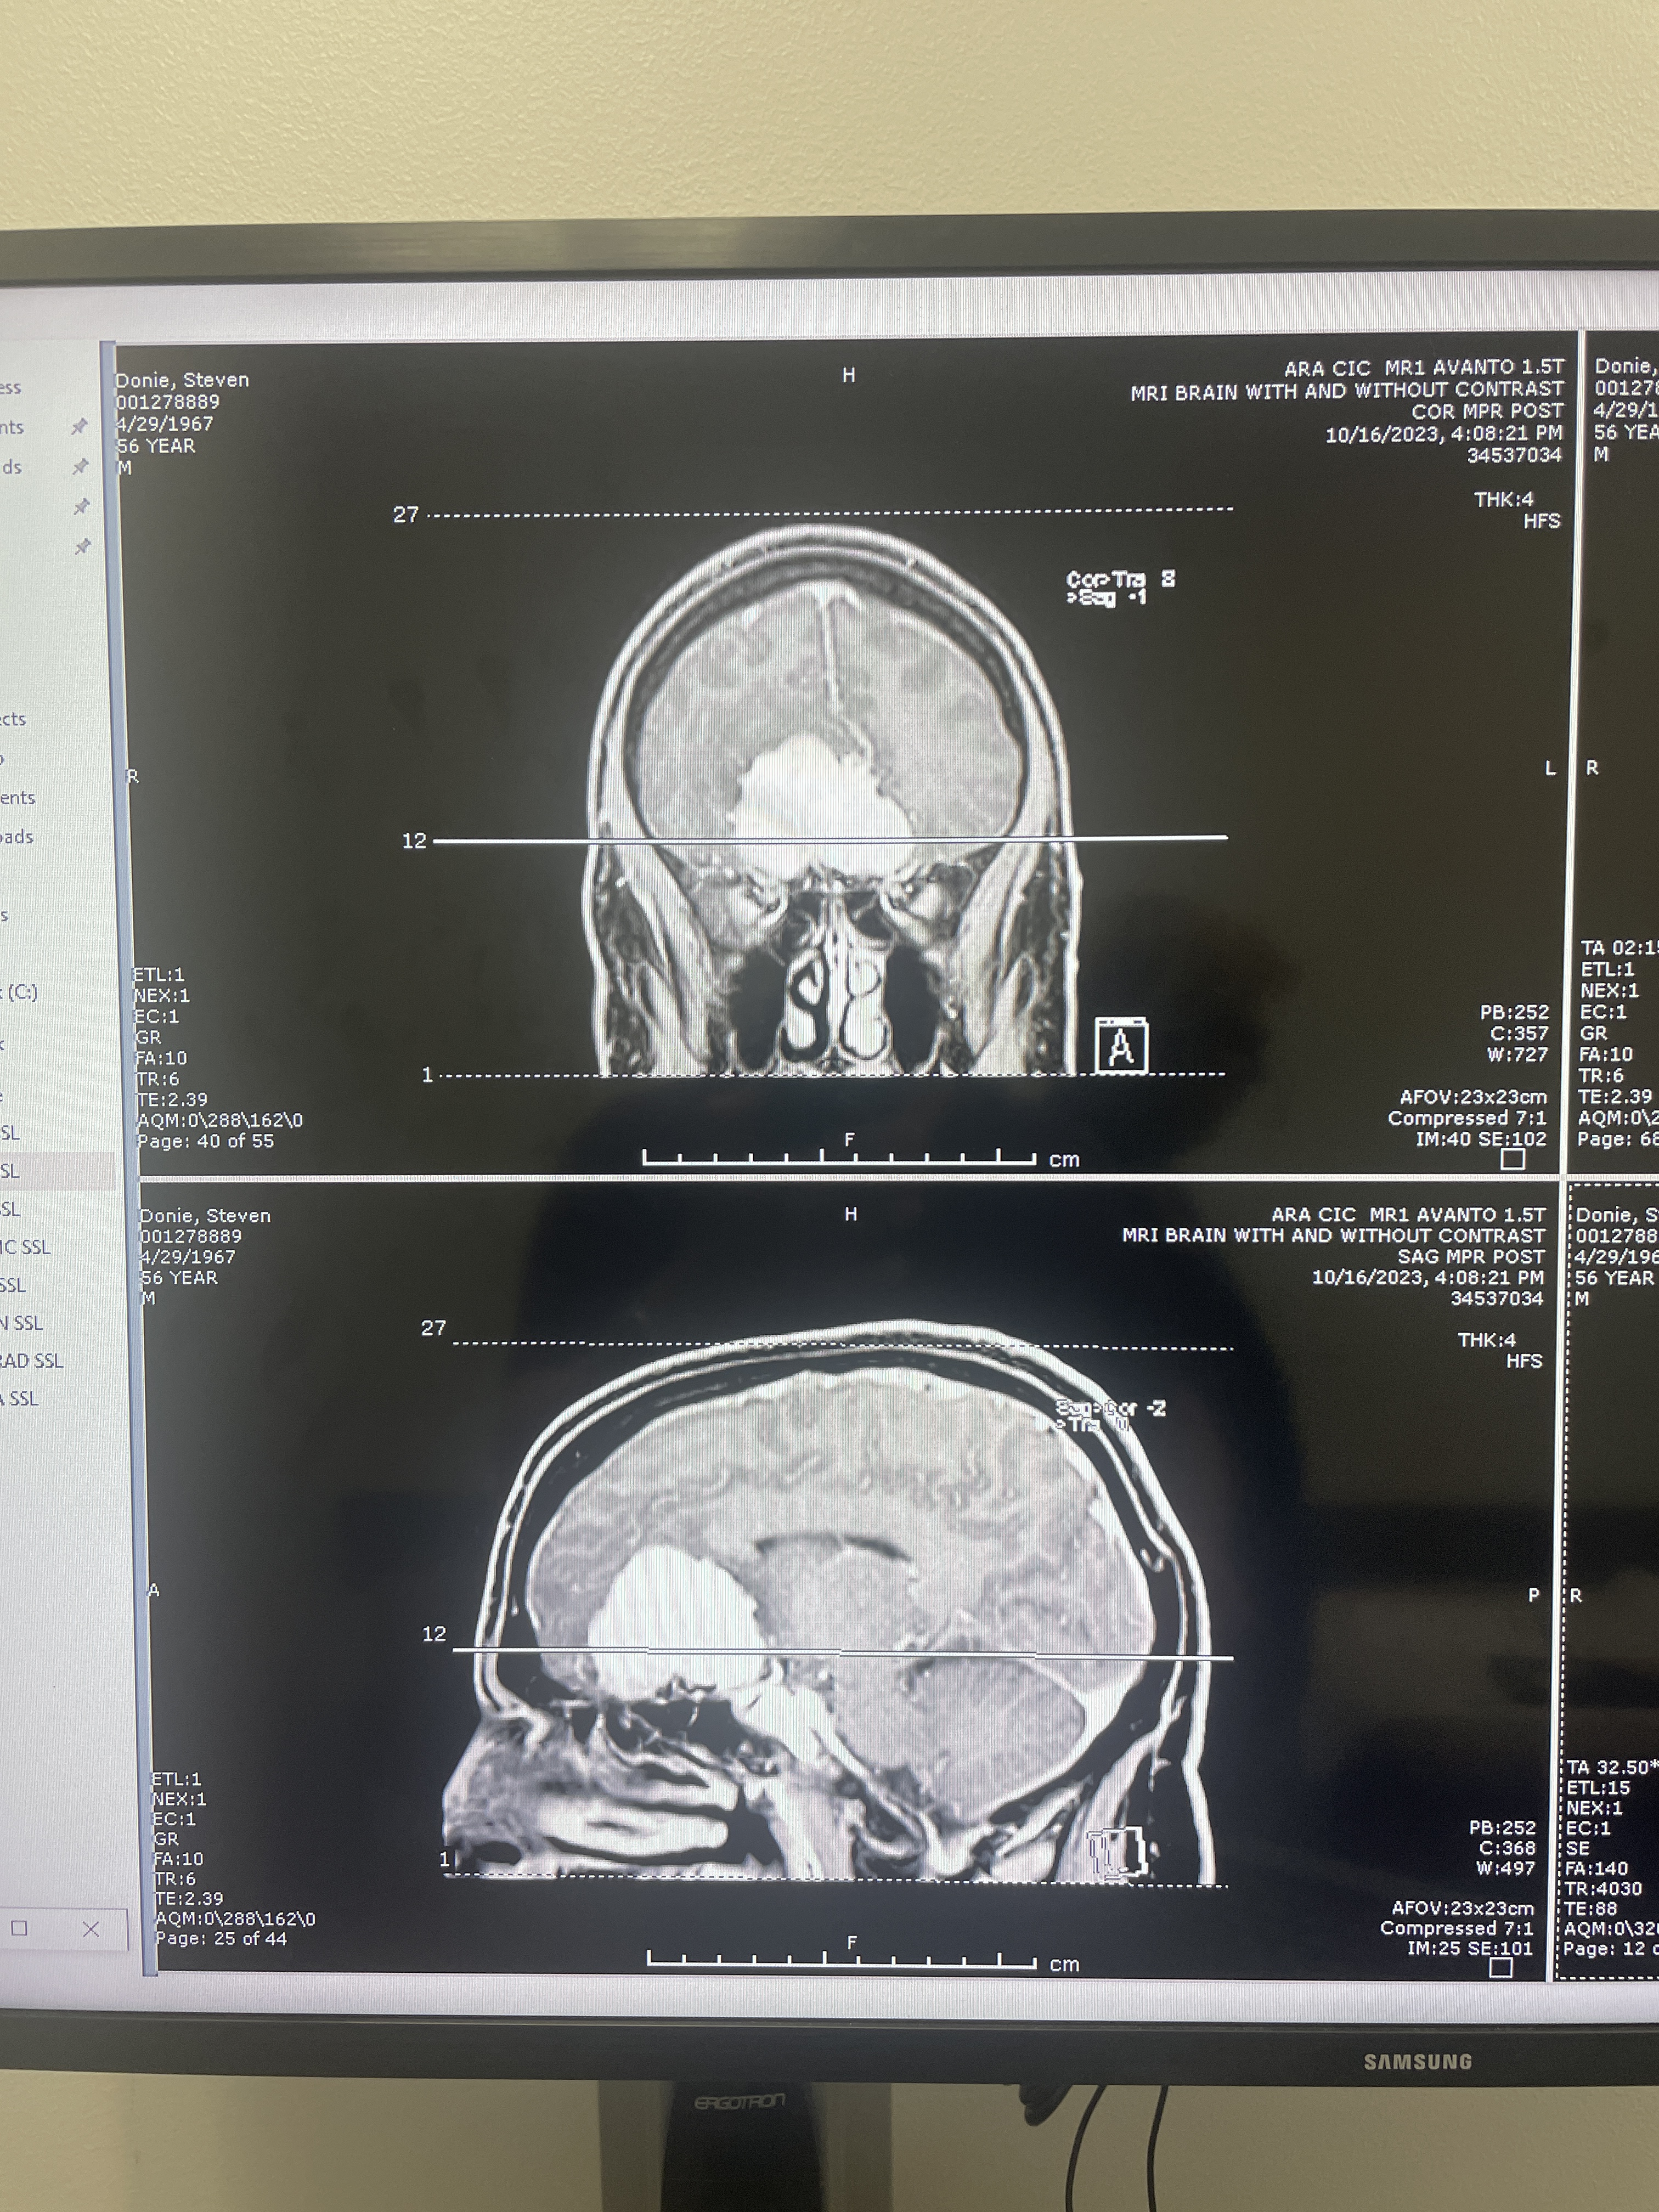

MRI, front and side views

This shows the tumor just above my nose. One of the side effects was that I lost my sense of smell. I had noticed that before the memory symptoms, but I first noticed it during the COVID outbreak, and attributed it to that. The surgeon said it is unlikely I will get my smell back.